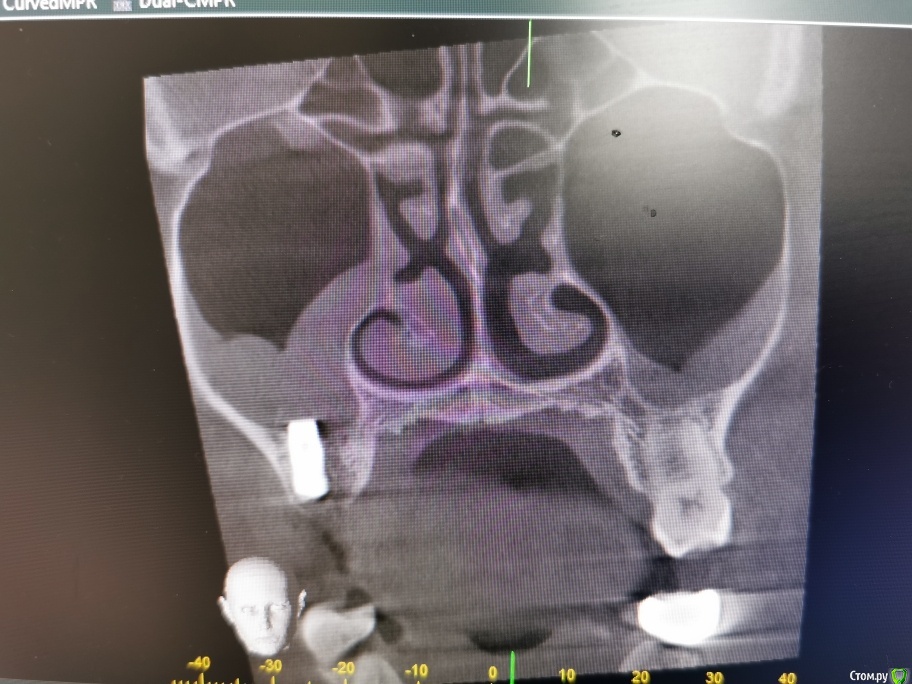

olga.maverick Опубликовано 1 марта, 2021 Поделиться Опубликовано 1 марта, 2021 (изменено) Здравствуйте!Вместо удалённого год назад зуба, 18 февраля врач установил мне в верхнюю челюсть имплант Импро, без синус лифтинга, сказал, что между слизистой и имплантом проложил губку, она рассосётся и кость нарастёт. Он сделал контрольный снимок-рентген, подтвердил, что имплант в пазухе, но под слизистой и это по его мнению норма. Пять дней я пила Амоксиклав по его назначению. Сегодня, первого марта сделала снимок КЛКТ, т.к. не проходит. насморк и дискомфорт в районе пазух.Получилась вот такая картина-сильный отёк в районе правой пазухи , до установки импланта отёка не было, есть снимок, сделанный перед операцией. Помогите пожалуйста разобраться:1) Всё идёт по плану, отёк временная реакция, имплант установлен профессионально или всё плохо?2)Нормально ли, что имплант стоит не посередине, а впритык к одному зубу? Изменено 1 марта, 2021 пользователем olga.maverick Ссылка на комментарий

olga.maverick Опубликовано 1 марта, 2021 Автор Поделиться Опубликовано 1 марта, 2021 (изменено) И, ещё, уважаемые доктора, если позволите вопрос. В левой пазухе у меня отёк уже несколько лет. Один маститый лор сказал, что у меня киста и он мне её удалит. Другой оперирующий лор сказал, что кисты нет, есть пломбировочный материал под слизистой, внутри пазухи ничего нет, кроме отёка слизистой.Мой врач (речь о котором в посте выше) утверждает, что в 27 зубе, максимально близко подходящем к пазухе, нет пломбы, зуб девственный. А я не помню, что и когда лечила. У вас есть версии, что за крапинка на снимке в левой пазухе и кому идти за решением, к лору или стоматологу)? Маюсь хроническим ринитом и периодическими гайморитами. Изменено 1 марта, 2021 пользователем olga.maverick Ссылка на комментарий